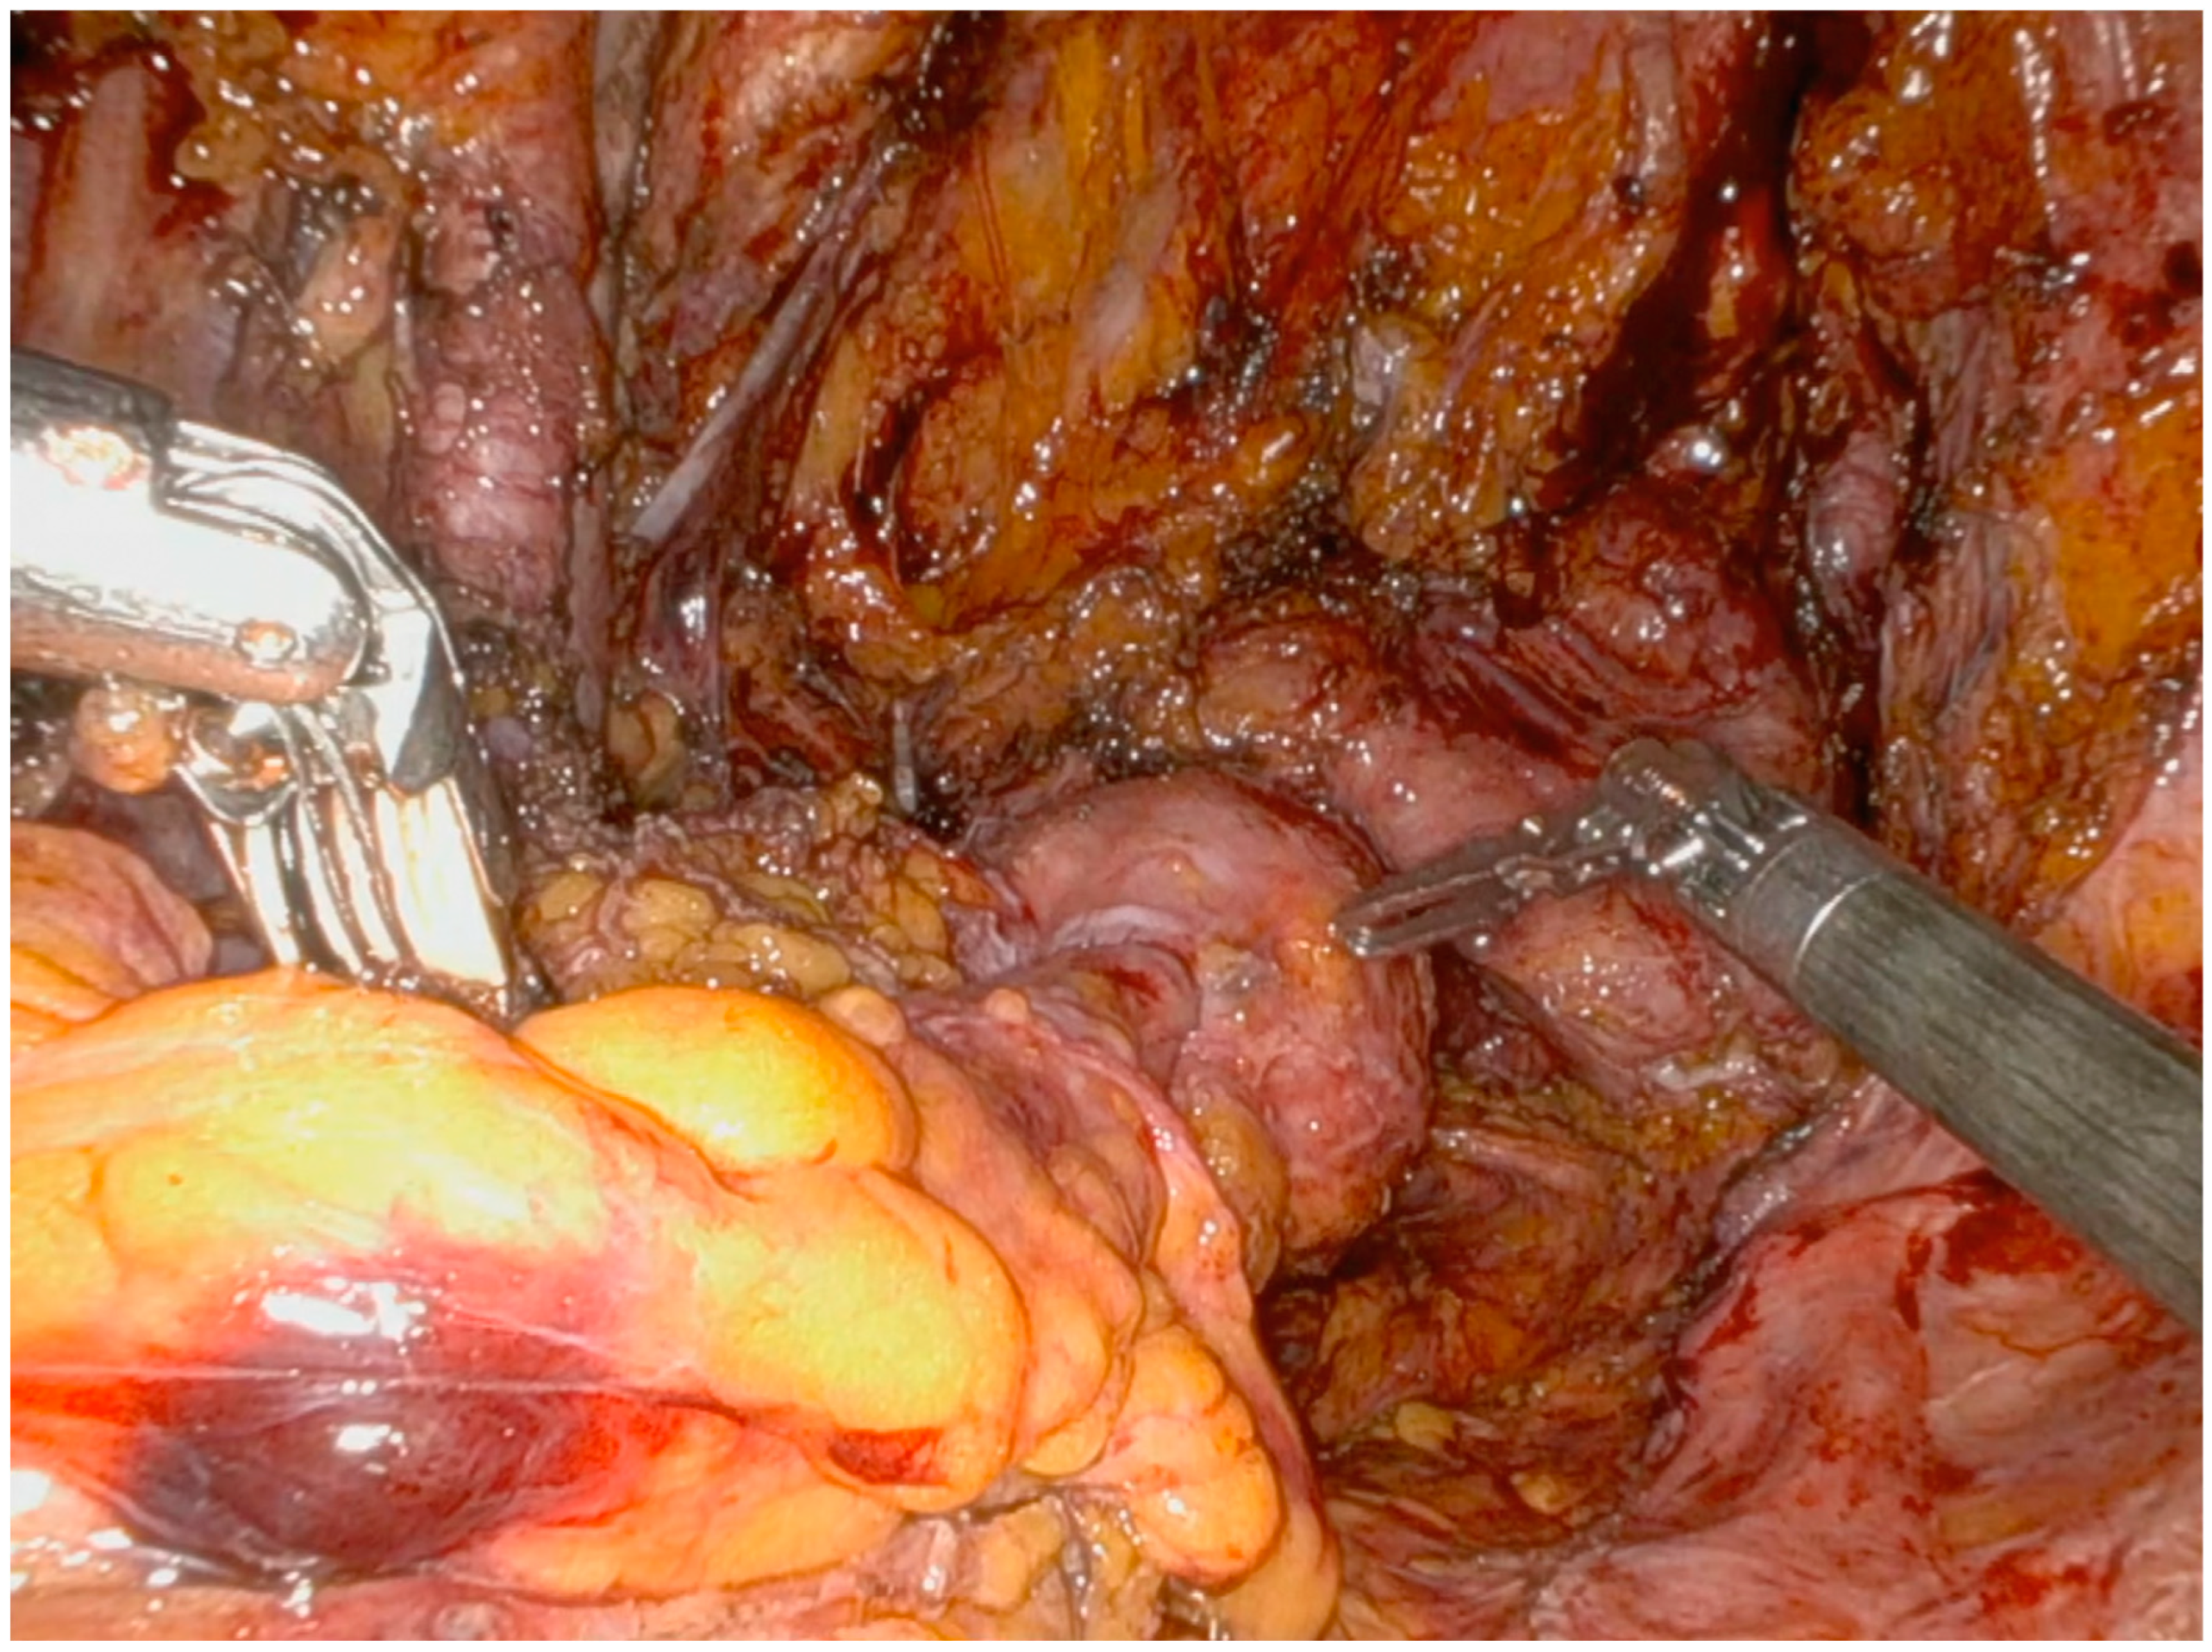

Operative Technique